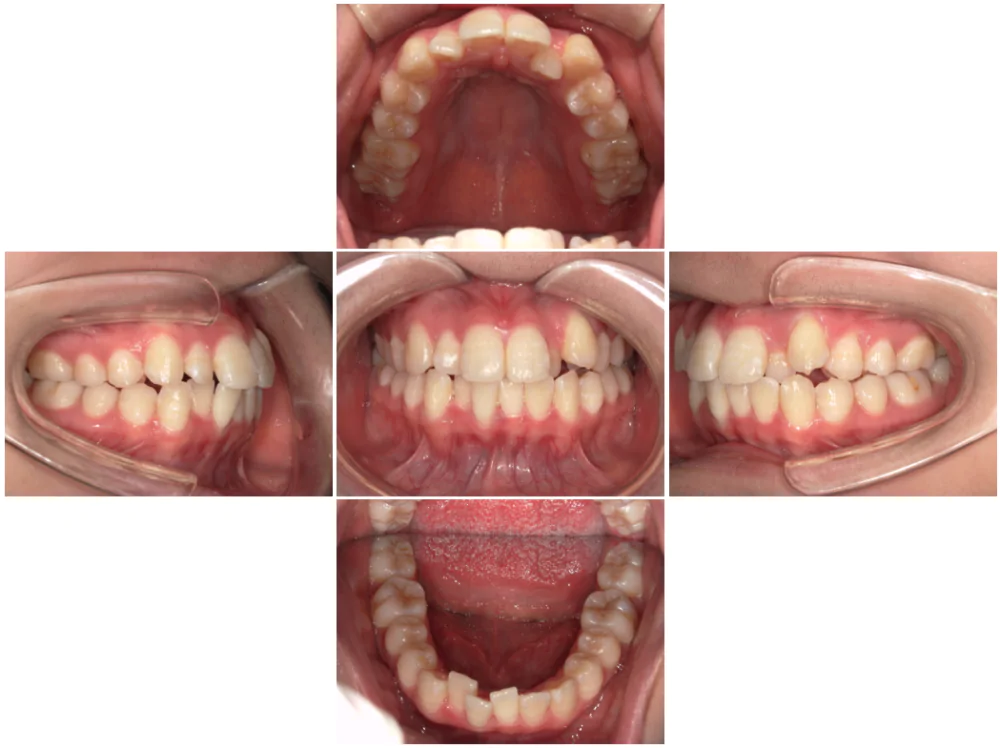

症例1

| 来院時の主訴 |

全体的なガタガタを治したい。

できれば抜歯はしたくない。

歯並びを気にせず笑えるようになりたい。

| 医院での対応や適用装置 | マウスピース矯正装置を使用して主訴であるガタガタを改善しました。 ガタガタの改善に必要なスペースの確保のために上あごの親知らずのみ抜歯を行いました。 |

| 通院期間 | 1年1ヶ月 |

| 通院回数 | 7回(治療中) |

| 治療費用総額 | 725,000円(税込) |

| リスクと副作用 | 矯正治療による歯の移動に伴う痛み、歯根吸収、虫歯 |